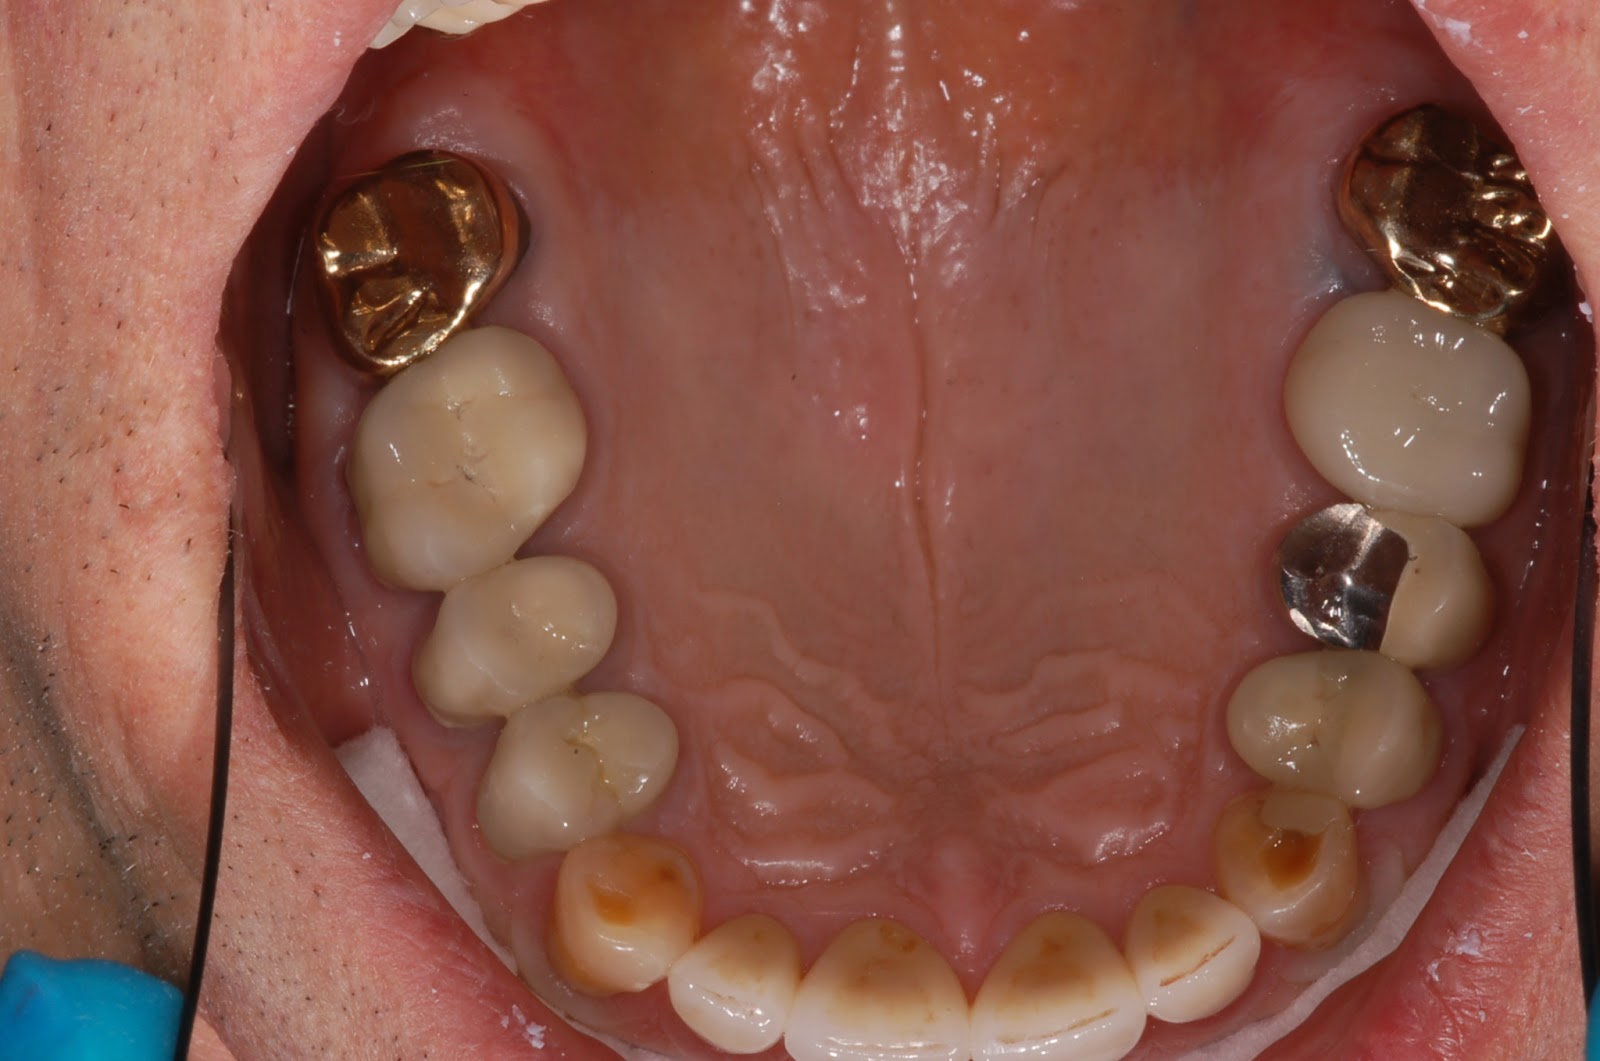

From www.bauersmiles.com

Dental wear of multiple dental materials Zirconia gold emax Dental Wear On dental wear is a general term that can be used to describe the surface loss of dental hard tissues from causes other than. patients with tooth wear present with a range of signs and symptoms of the condition, from mild tooth wear,. The three main types of tooth wear are erosion, abrasion and attrition. wear on teeth. Dental Wear On.